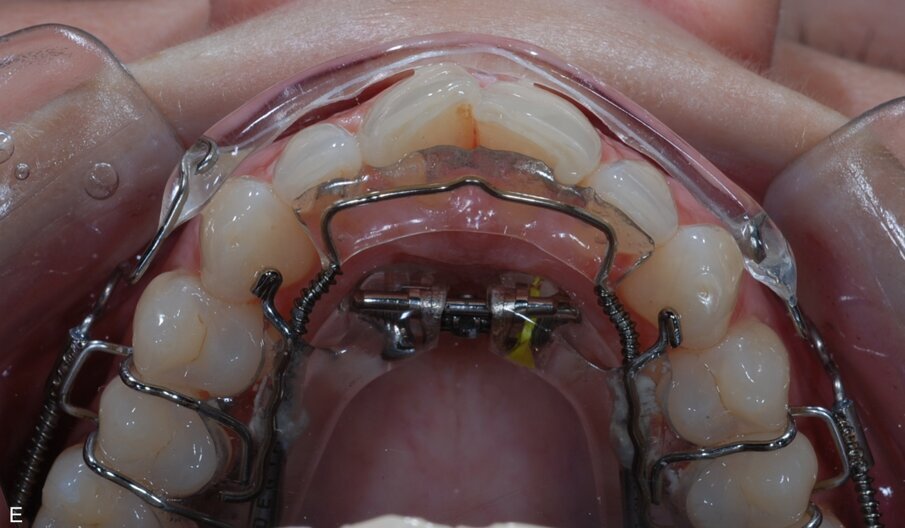

Fig. 9: ClearSmile Inman Aligner fitted

At the initial appointment, palatal anchors were placed, with interproximal reduction (IPR) and predictive proximal reduction (PPR) carried out using the guide issued from the laboratory. The patient was instructed on how to turn the expander. Aligner in situ. At the initial appointment, palatal anchors were placed, with interproximal reduction (IPR) and predictive proximal reduction (PPR) carried out using the guide issued from the laboratory. The patient was instructed on how to turn the expander. Aligner in situ. |